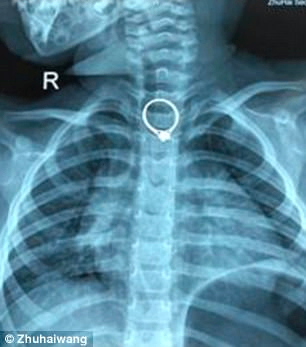

3: 반지